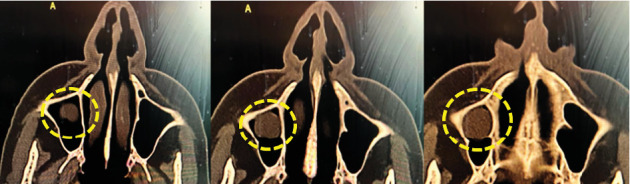

上颌窦潴留囊肿(msrc)是一种良性的充满液体的病变,通常在x线影像上偶然发现。虽然通常无症状,但较大的囊肿可能由于周围窦结构的压力而导致临床症状。本文报告一例罕见的MSRC症状病例,患者为70岁女性,有上颌磨牙拔牙后鼻窦穿孔病史。患者经历了严重的单侧面部疼痛、鼻塞、头痛和头晕,持续了6个月。x线影像(CT扫描)显示右侧上颌窦有一界限清楚的圆顶状病变,无骨侵蚀征象。鉴于保守治疗的失败和症状的强度,通过Caldwell-Luc入路进行手术干预。术中,囊性病变被去核并送去组织病理检查。组织学证实为呼吸上皮内衬的良性保留囊肿,伴炎症浸润和不寻常的胆固醇结晶,这在msrc中并不常见。患者的鼻窦穿孔史可能导致慢性炎症和囊肿形成。本病例强调了在出现非典型鼻窦症状的患者中考虑牙齿病史的重要性,特别是以前的上颌磨牙拔牙累及鼻窦。虽然内窥镜鼻窦手术通常是首选的方法,但Caldwell-Luc手术在某些解剖结构复杂或既往手术改变的病例中仍然有价值。临床医生应该意识到msrc的罕见表现可能需要量身定制的手术治疗来缓解症状和预防复发。

Maxillary sinus retention cysts (MSRCs) are benign, fluid-filled lesions most often discovered incidentally on radiographic imaging. Although typically asymptomatic, larger cysts may lead to clinical symptoms due to pressure on surrounding sinus structures. This report presents a rare symptomatic case of an MSRC in a 70-year-old female patient with a prior history of sinus perforation following upper molar extraction. The patient experienced severe unilateral facial pain, nasal congestion, debilitating headaches, and dizziness over a 6-month period. Radiographic imaging (CT scan) revealed a well-circumscribed, dome-shaped lesion in the right maxillary sinus without signs of bone erosion. Given the failure of conservative management and the intensity of symptoms, surgical intervention via the Caldwell-Luc approach was performed. Intraoperatively, the cystic lesion was enucleated and sent for histopathological examination. Histology confirmed a benign retention cyst lined with respiratory epithelium, along with inflammatory infiltrates and the unusual presence of cholesterol crystals, which is an uncommon finding in MSRCs. The patient's history of sinus perforation likely contributed to chronic inflammation and cyst formation. This case emphasizes the importance of considering dental history, particularly previous maxillary molar extractions with sinus involvement, in patients presenting with atypical sinus symptoms. While endoscopic sinus surgery is often the preferred approach, the Caldwell-Luc procedure remains valuable in selected cases with complex anatomy or previous surgical alterations. Clinicians should be aware of rare presentations of MSRCs that may require tailored surgical management for symptom resolution and recurrence prevention.